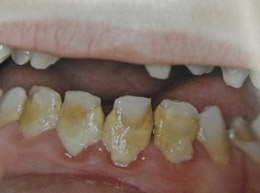

Υπενασβετίωση της αδαμαντίνης

Συνήθως εκδηλώνεται με λευκές, κίτρινες ή καφέ κηλίδες στους τομείς και τους γομφίους, μπορεί όμως να επηρεάσει και άλλα δόντια. Η κλινική εικόνα μπορεί να περιορίζεται μόνο στην εμφάνιση αυτών των κηλίδων, ή να είναι πιο σοβαρή προκαλώντας απώλεια της αδαμαντίνης του δοντιού, με συνέπεια την εμφάνιση ευαισθησίας και πόνου καθώς και τερηδόνας.

Η κατάσταση αυτή της αδαμαντίνης οφείλεται σε διαταραχή της διάπλασής της με αποτέλεσμα την ελλιπή ενσωμάτωση των μετάλλων στη δομή της. Έχουν ενοχοποιηθεί διάφοροι παράγοντες (περιβαλλοντικοί, ασθένειες της μητέρας και του βρέφους, διατροφή κ.ά.) οι οποίοι μπορούν να προκαλέσουν αυτές τις διαταραχές.

Σημαντική είναι η έγκαιρη διάγνωση από τον παιδοδοντίατρο και η εφαρμογή ενός ολοκληρωμένου προληπτικού προγράμματος προστασίας αυτών των δοντιών προκειμένου να διατηρηθούν υγιή.